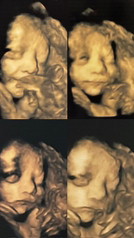

หนุ่มน้อนในวัย 30วีค ยิ้มกรุ้มกริ่มในท้องแม่ ❤️🫶🧸